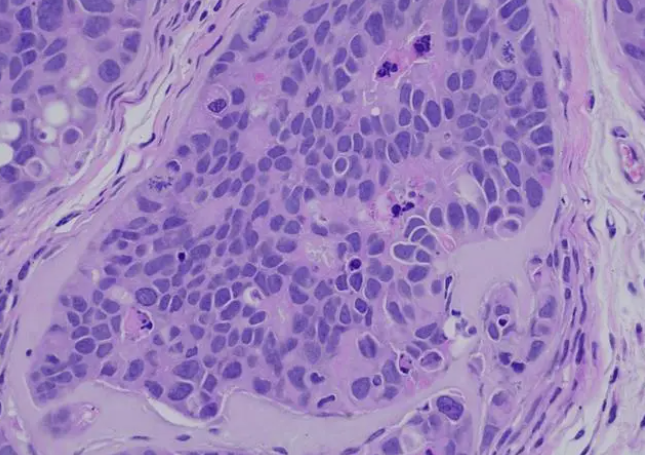

蘇木精 — 伊紅染色法 ,簡(jiǎn)稱(chēng)HE染色法 ,石蠟切片技術(shù)里常用的染色法之一 。蘇木精染液為堿性 ,主要使細(xì)胞核內(nèi)的染色質(zhì)與胞質(zhì)內(nèi)的核酸著紫藍(lán)色 ;伊紅為酸性染料 ,主要使細(xì)胞質(zhì)和細(xì)胞外基質(zhì)中的成分著紅色 。HE染色法是組織學(xué)、胚胎學(xué)、病理學(xué)教學(xué)與科研中最基本、使用最廣泛的技術(shù)方法。

脫氧核糖核酸兩條鏈上的磷酸基向外,帶負(fù)電荷,呈酸性,很容易與帶正電荷的蘇木精堿性染料以離子鍵結(jié)合而被染色。蘇木精在堿性溶液中呈藍(lán)色,所以細(xì)胞核被染成藍(lán)色。伊紅Y是一種化學(xué)合成的酸性染料,在水中離解成帶負(fù)電荷的陰離子,與蛋白質(zhì)的氨基正電荷的陽(yáng)離子結(jié)合使胞漿染色,細(xì)胞漿、紅細(xì)胞、肌肉、結(jié)締組織、嗜伊紅顆粒等被染成不同程度的紅色或粉紅色,與藍(lán)色的細(xì)胞核形成鮮明對(duì)比。伊紅是細(xì)胞漿的良好染料。

由于組織或細(xì)胞的不同成分對(duì)蘇木精的親和力不同及染色性質(zhì)不一樣。經(jīng)蘇木精染色后,細(xì)胞核及鈣鹽粘液等呈藍(lán)色,可用鹽酸酒精分化和弱堿性溶液顯藍(lán),如處理適宜,可使細(xì)胞核著清楚的深藍(lán)色,胞漿等其它成分脫色。再利用胞漿染料伊紅染胞漿,使胞漿的各種不同成分又呈現(xiàn)出深淺不同的粉紅色。故各種組織或細(xì)胞成分與病變的一般形態(tài)結(jié)構(gòu)特點(diǎn)均可顯示出來(lái)。